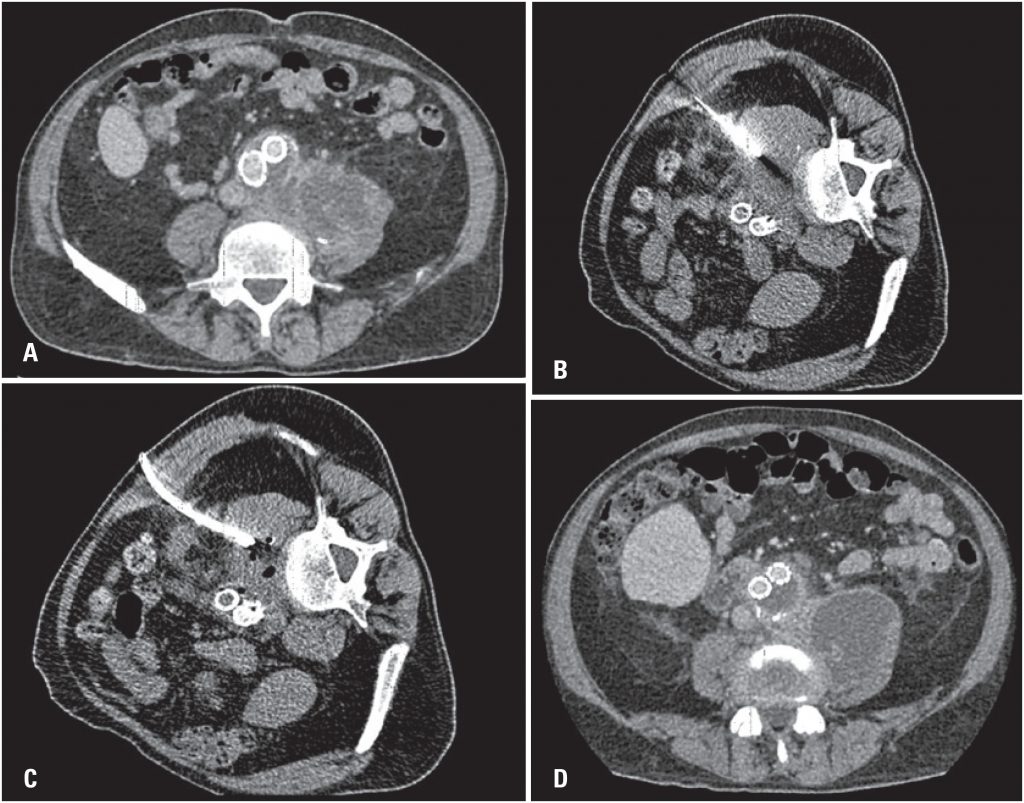

The aim of this study were to describe the technique of percutaneous drainage of iliopsoas abscess, and to discuss the benefits of using this minimally-invasive tool. A single center study with retrospective analysis of patients with psoas abscess confirmed by imaging scans, sent to the interventional medicine center and submitted to computed tomography and ultrasound-guided percutaneous drainage, from November 2013 to August 2016. Seven patients underwent percutaneous drainage of psoas abscess in this period. The mean initial drained volume was 61.4±50.7mL (ranging from 10 to 130mL), and the mean drainage duration was 8.3±2.8 days (ranging from 4 to 12 days). The success rate of the percutaneous procedures was 71.5%, and two patients required re-intervention. Image-guided percutaneous drainage of iliopsoas abscess is a minimally invasive, efficient and safe procedure, and an extremely valuable technique, especially for patients who are not suitable for surgical repair.